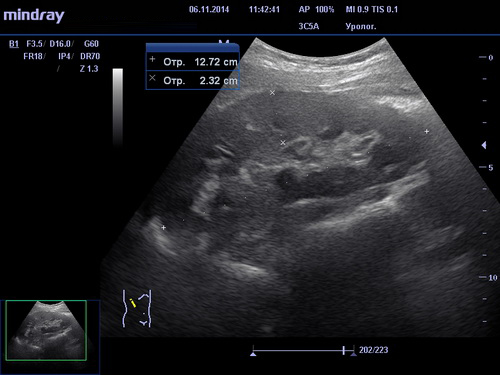

Проведение процедуры

Необходимо раздеться до пояса и лечь на кушетку. Врач, проводящий исследование нанесёт специальный гипоаллергенный гель на участки исследования для лучшего скольжения датчика и беспрепятственного прохождения ультразвуковых волн. Вся процедура занимает не более двадцати минут. Программное обеспечение позволяет создать модель работающего органа и увидеть все возможные изменения, происходящие с ним. После окончания исследования пациент получит на руки письменный результат с рекомендациями врача.

Какие заболевания может выявить УЗИ почек?

Исследование почек поможет определить и выявить следующие заболевания:

- присутствие в почечных лоханках камней или песка;

- наличие любых новообразований как доброкачественных, так и злокачественных;

- изменение чашечно-лоханочной системы;

- стеноз почечных артерий;

- изменения в сосудах почек;

- пиелонефрит на ранних стадиях.

Наши клиники проводят полное УЗИ почек в Москве с помощью самых современных технологий. Допплерографическое исследование помогает обследованию кровеносных сосудов, благодаря чему становится видны любые изменения в кровоснабжении почек. Одновременно с обследованием почек может проводиться ультразвуковое обследование мочевого пузыря для выстраивания полной картины работы мочеполовой системы пациента.